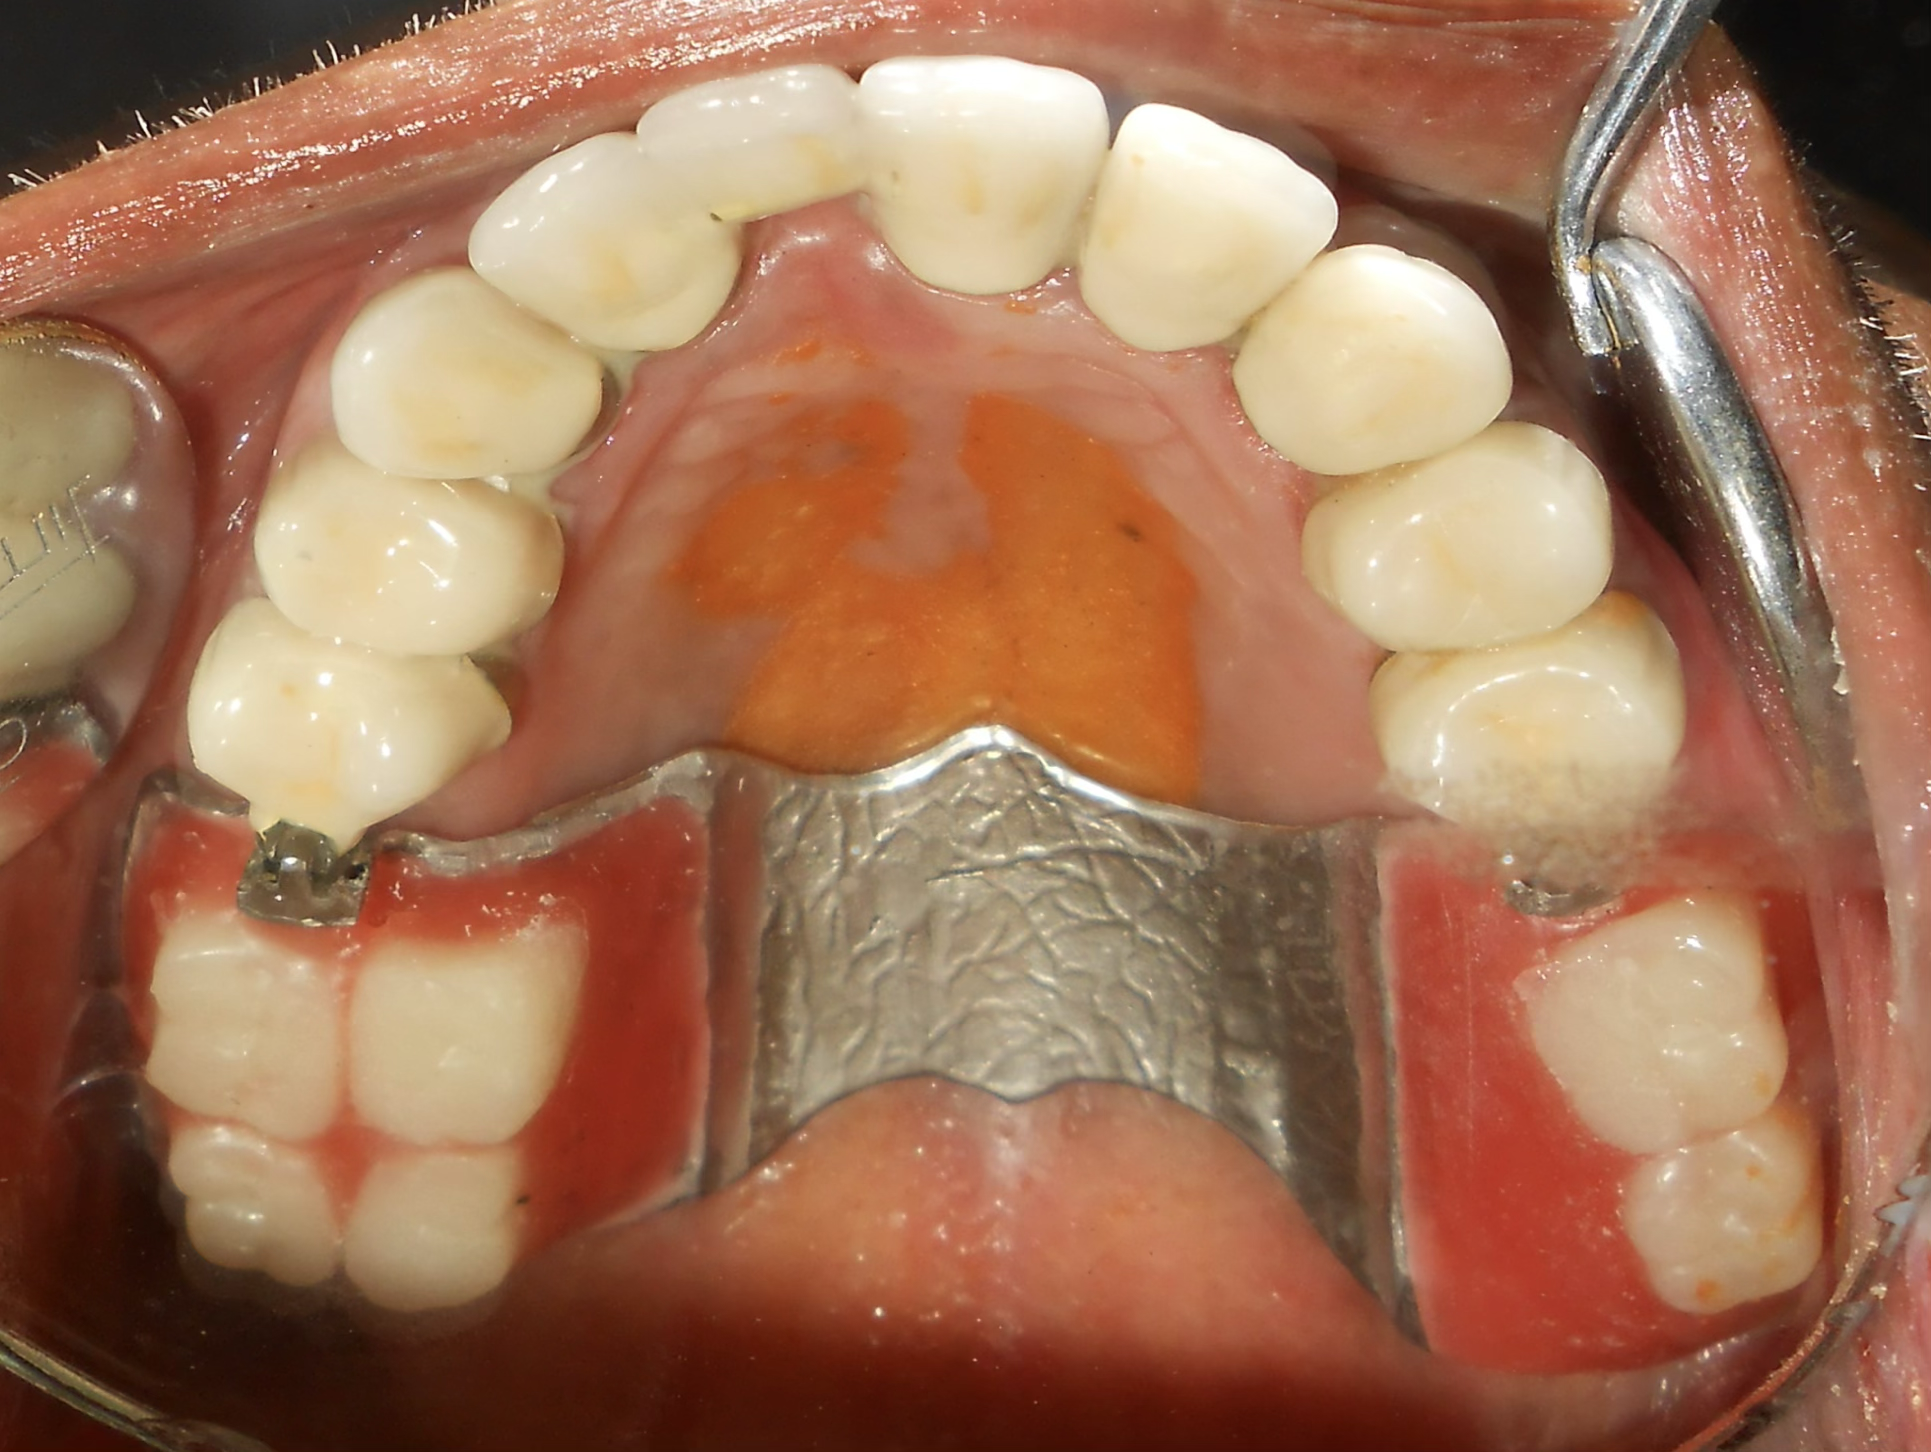

Comprehensive evaluation of oral cancer survivor post-hemimandibulectomy. Patient presented with missing teeth 16, 17, 25, 26, 31-37 and excised right mandible. Complete assessment of remaining bone and soft tissue.

Strategic placement of 4 Dio dental implants in the regions 32, 33, 35, and 36 using advanced surgical techniques suitable for post-cancer reconstructed anatomy.

PFM crowns were fabricated and fixed for the upper remaining teeth to restore function and aesthetics.